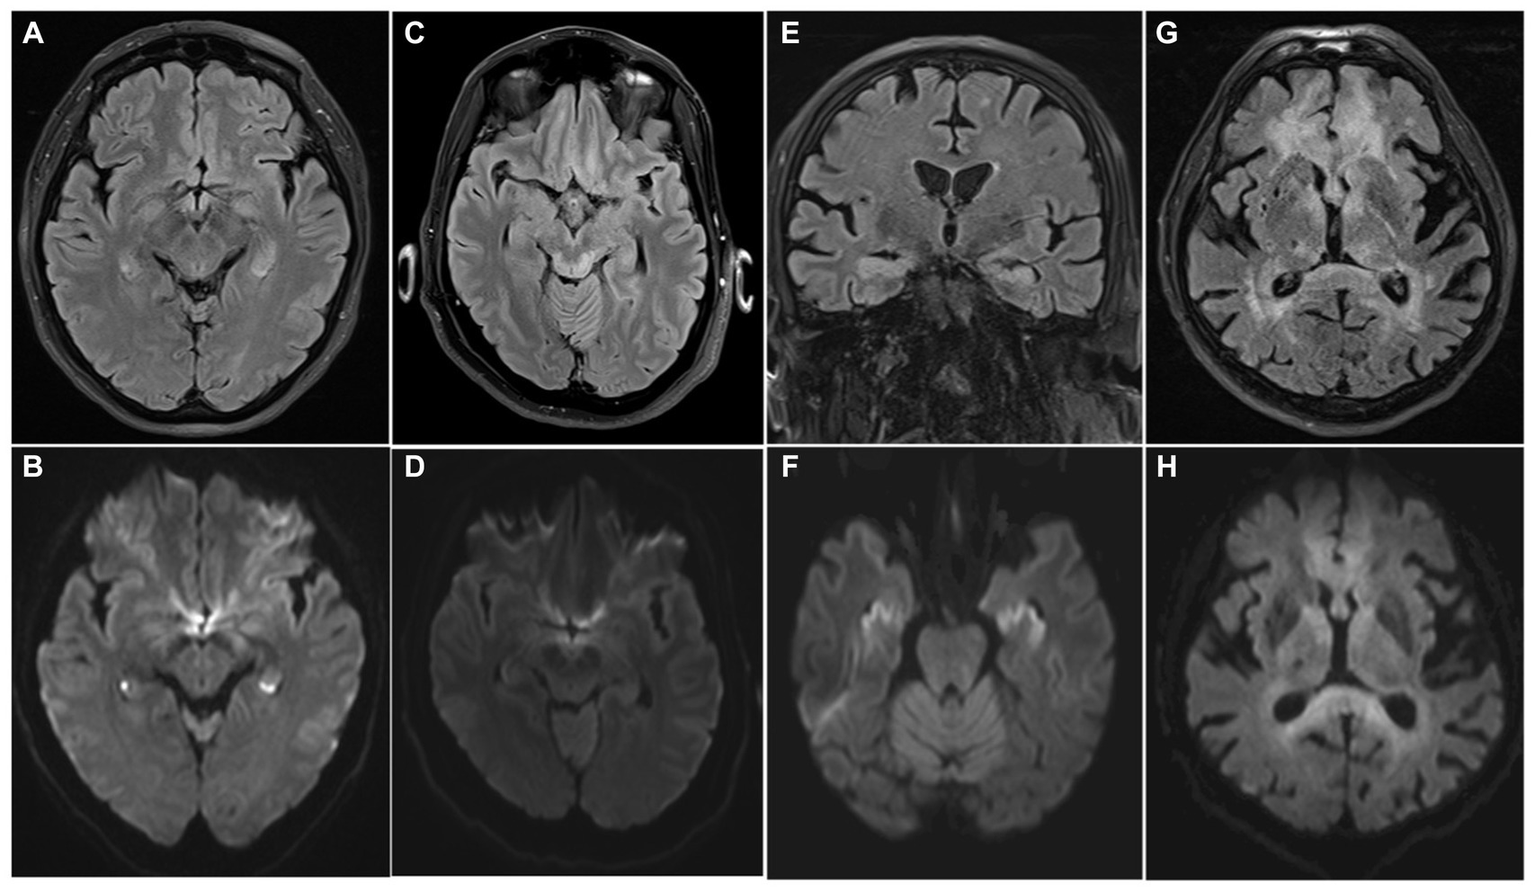

Several neurological diseases should be considered in the differential diagnosis. TGA is the most common and typically presents with isolated anterograde amnesia with a limited retrograde component. Focal neurological deficits are absent, and the transient nature of the memory deficit is a key element for diagnosis, but of limited utility during the acute evaluation. MRI can demonstrate hippocampal punctate diffusion lesions (HPDL) (Figures 5A,B) or rarely extra-hippocampal punctate diffusion lesions (E-HPDL), but it can also be normal (88, 89).

Figure 5

MRI differential diagnosis of acute amnestic syndrome. Transient global amnesia (A,B), Wernicke-Korsakoff syndrome (C,D), limbic encephalitis (E,F), and lymphoma (G,H) can present with acute anterograde amnesia, with or without other neurological symptoms. Bilateral HPDLs in a case of TGA are showed (A) (FLAIR) and (B) (DWI). Typical tectal plate lesions associated with alcoholic Wernicke-Korsakoff syndrome are showed in FLAIR and DWI sequences (C,D). MRI shows bilateral hyperintensity of the hippocampi on both FLAIR (E) and DWI (F) sequences in a case of paraneoplastic limbic encephalitis. A central nervous system lymphoma involving the fornix, but also frontal lobes and periventricular withe matter is showed in (G) (FLAIR) and (H) (DWI), appearing as a diffuse hyperintense alteration on both sequences.

Wernicke-Korsakoff syndrome is another mimic, but the medical history often reveals the cause of the thiamine deficit aiding in the diagnostic process; MRI can show hyperintensity in T2/FLAIR in mammillary bodies, medial thalami, hypothalamus, tectal plate, periaqueductal area; rarer in cerebellum, brainstem, basal ganglia (Figures 5C,D) (90, 91).

Limbic encephalitis (Figures 5E,F), dissociative amnesia and neoplasms as lymphoma (Figures 5G,H) are other potential differential diagnosis but are usually more easily distinguishable from the clinical characteristics, and amnesia is rarely the only neurological symptom. The principal characteristics of the main pathologies included in the differential diagnosis are summarized in Table 4.